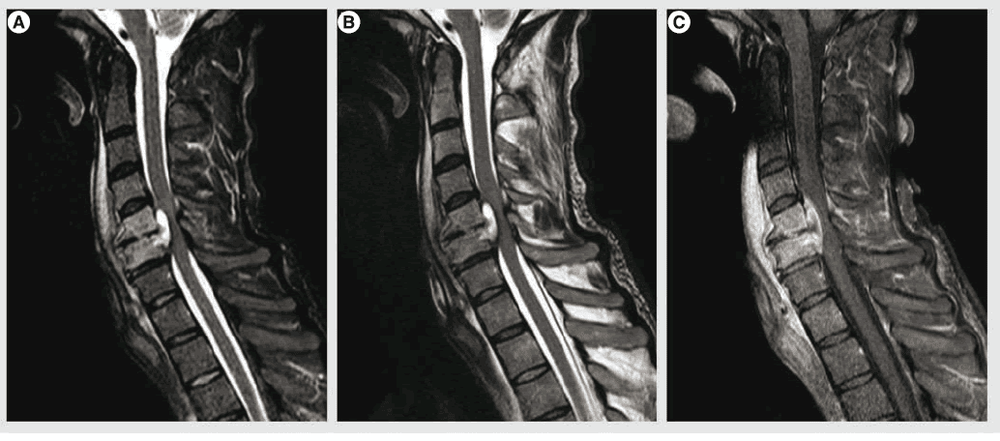

Áp xe ngoài màng tủy là căn bệnh do khối mủ nằm giữa khoang ngoài màng tủy và ống sống. Nguyên nhân dẫn đến bệnh là do nhiễm trùng như lao cột sống, nhiễm trùng sau phẫu thuật,… Bệnh nếu không được chẩn đoán và điều trị thì sẽ dẫn đến nguy cơ gây liệt và tàn phế vĩnh viễn.

Tùy vị trí và mức độ chèn ép của khối áp xe mà biểu hiện liệt có thể ở hai chi dưới hoặc ở cả hai tay và chân với các mức độ từ nhẹ đến nặng như giảm cảm giác, giảm vận động cho đến mất vận động và mất cảm giác hoàn toàn.

Bên cạnh đó, người bệnh có thể bị rối loạn đại tiểu tiện, thậm chí rối loạn hô hấp và có thể dẫn đến tử vong. Nguyên nhân bệnh nhân bị liệt là do khối áp xe chèn ép trực tiếp vào tủy hay còn gọi là áp xe tủy não hoặc do nhiễm trùng gây ra tắc mạch làm thiếu máu vùng tủy, gây tổn thương tủy.